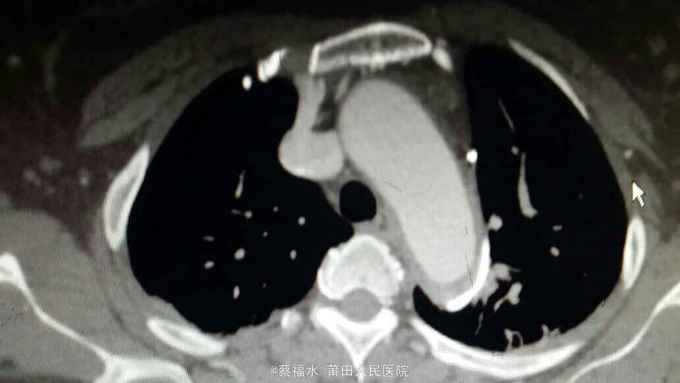

女性患者,56岁,以“上腹部、左腰部突发疼痛2小时”为主诉入院。入院查体:HR70次/分,BP220/105mmHg,双肺呼吸音清,未闻及干湿性啰音,心律齐,各瓣膜区未闻及杂音,腹平软上腹部压痛明显,无反跳痛,胆囊区无压痛,墨菲氏征阴性,肝脾肋下未及,左肾区叩痛可疑阳性,肠鸣音约5次/分。入院后查血淀粉酶正常,肌钙蛋白I阴性,心肌酶谱正常,心电图无心肌缺血改变,上腹部+胸部CT提示:右肾囊肿,余未见明显异常。予抑酸、维生素K3、曲马多等应用后,患者仍腹痛剧烈,性质同前,无明显缓解。予完善胸主动脉、腹主动脉、髂动脉CTA结果如下:

腹主动脉夹层动脉瘤 予控制血压、控制心率等治疗,患者腹痛较前缓解